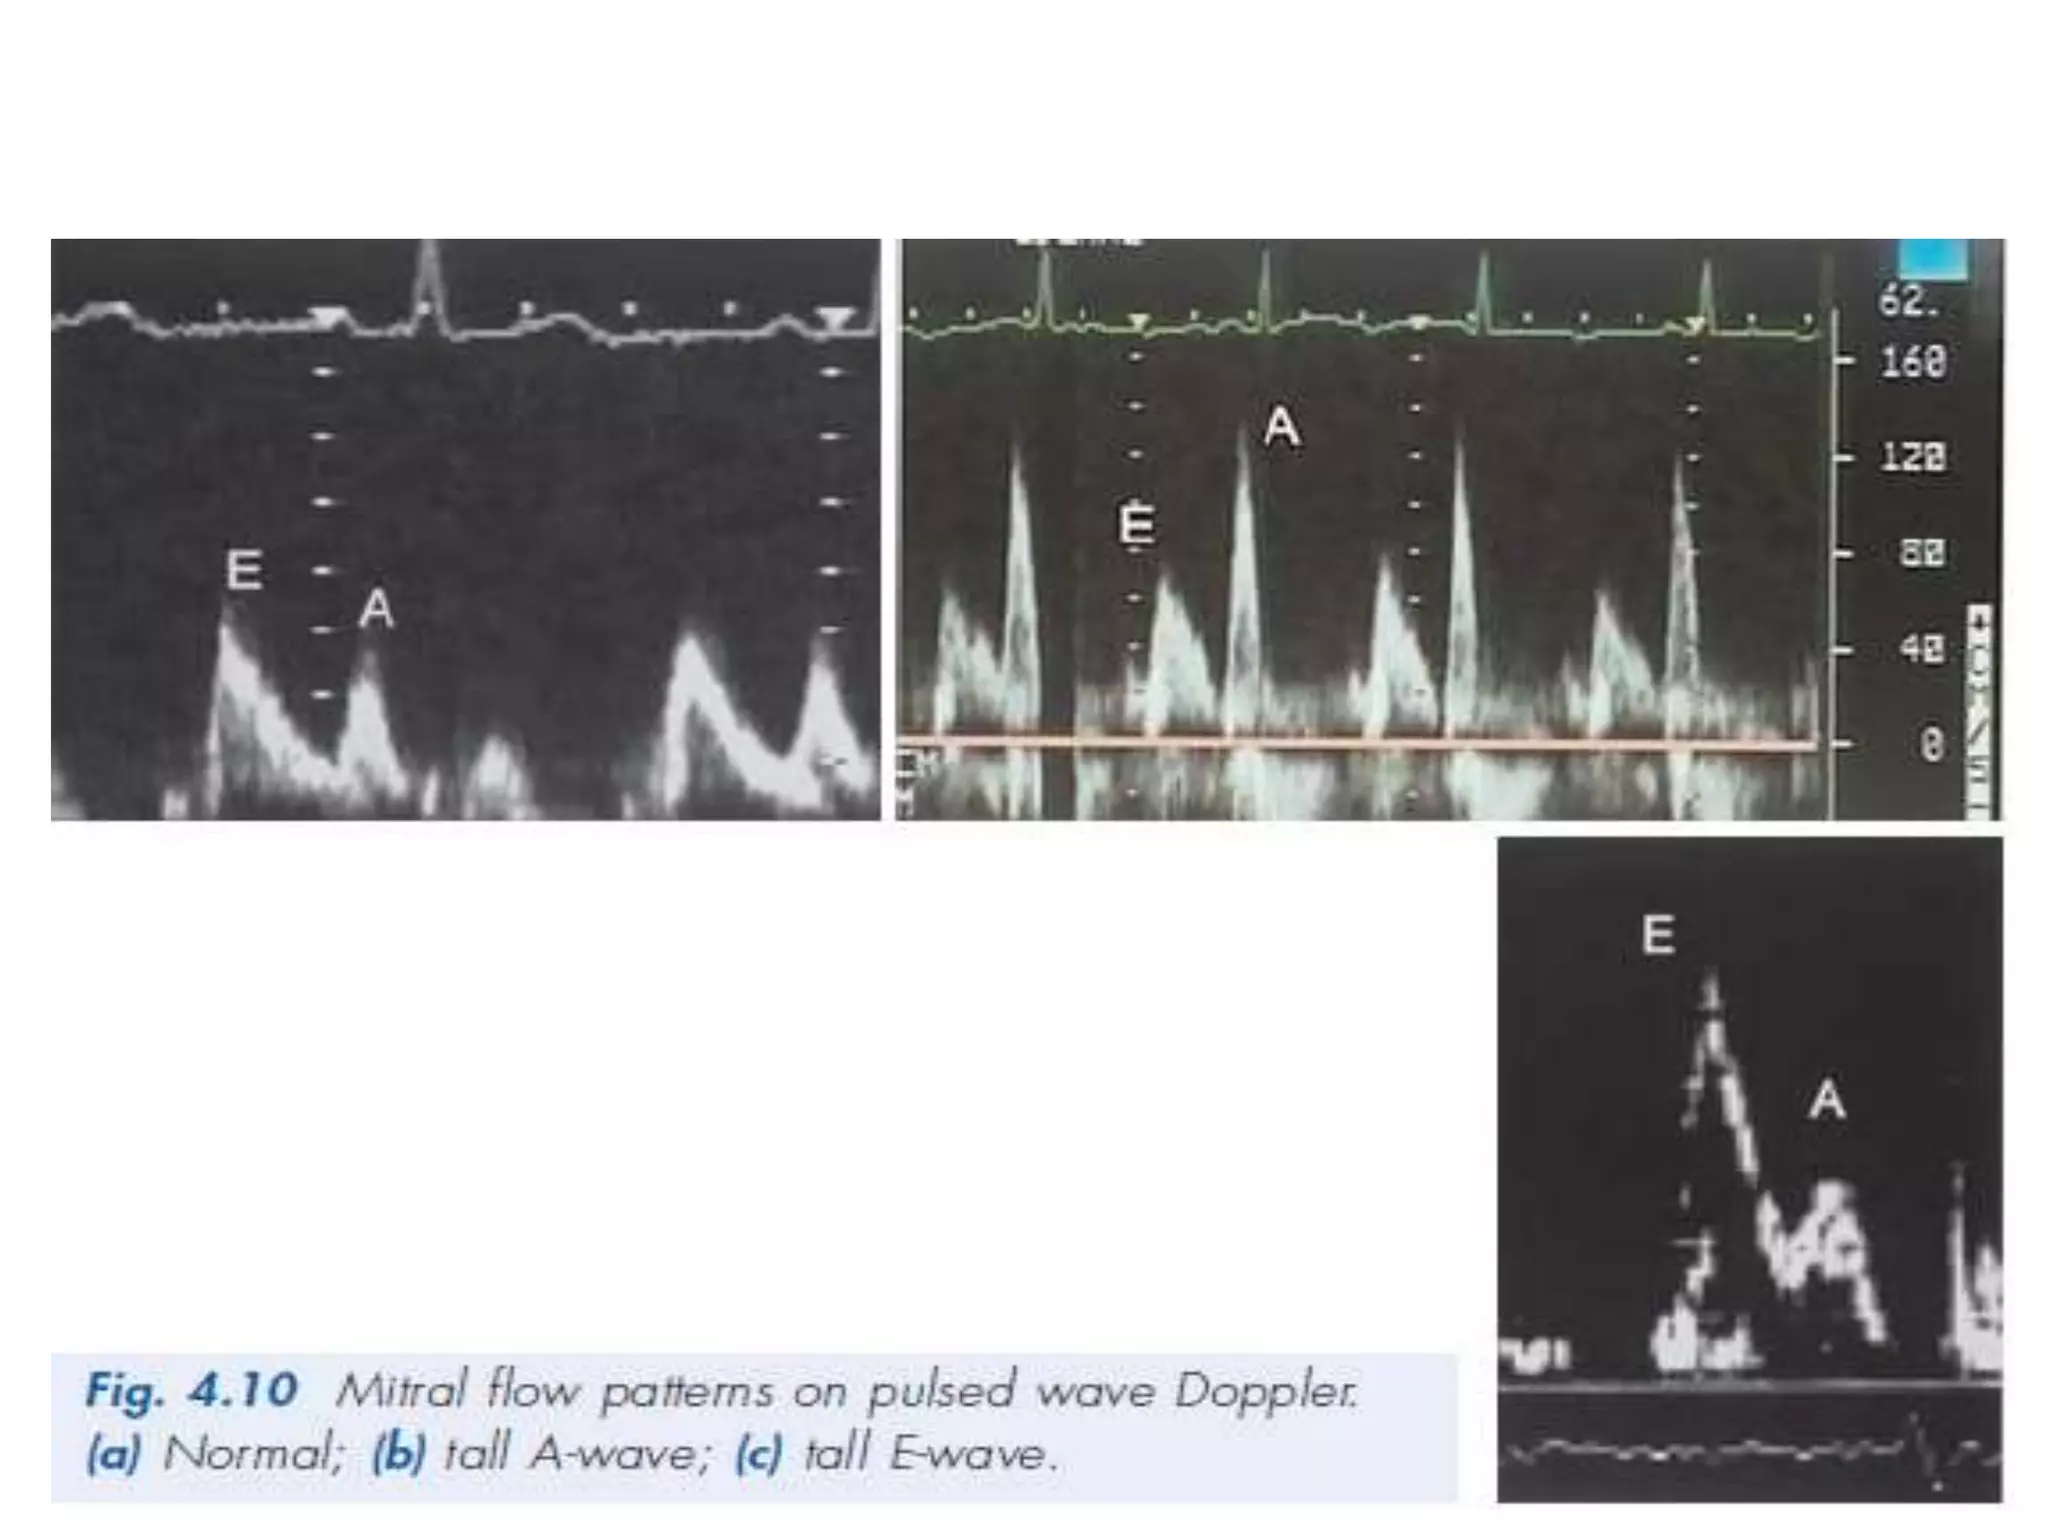

Pulsed wave Doppler

• ● Normal valve flow patterns

• ● LV diastolic function

• ● Stroke volume and cardiac output.